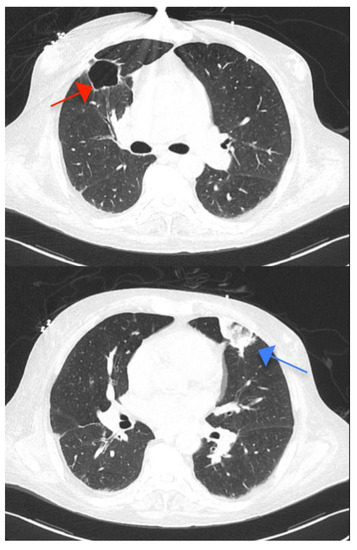

There was a subacute right occipital stroke and splenomegaly with splenic infarctions, both of which were interpreted as embolic consequences of the IE (Figure 4).

Four cavities in the lungs were identified as tuberculosis sequelae (Figure 5); however, two lobar consolidations raised the possibility of tuberculosis reactivation, which was later excluded by negative sputum smear, presumably indicating embolization from the right-sided IE. Additional coronary CT angiography showed no significant stenosis in the coronary arteries.

Figure 4. (A) Cerebral computed tomography (CT) demonstrating subacute right occipital stroke (arrow) and (B) abdominal CT showing one of the splenic infarctions (arrow).